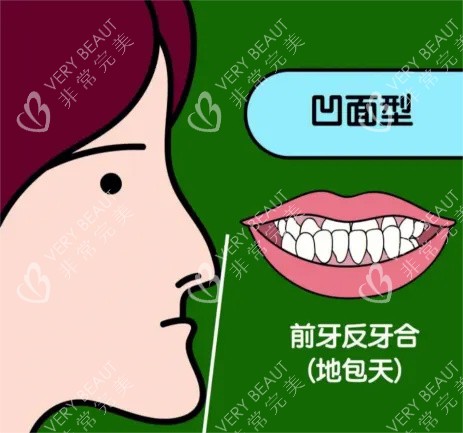

后来才知道,正颌手术分两种:一种是单纯牙性“地包天”,戴牙套就能矫正;另一种是骨性“地包天”,下巴骨头比上颌突出,必须动骨头。而我,属于后者。

更让我破防的是医生那句:“你现在的侧脸,像‘月亮脸’,做完手术会变‘直面型’,侧颜线条更流畅。”我摸着下巴,突然想起小学同桌的话——原来不是“像铲子”,是“像月亮”,而我要做的,是把“月亮”掰回“直线”。

正颌手术真的只是“变漂亮”吗?

——不,是终于不用再躲镜头的轻松,是别人看你侧脸时不再皱眉的释然,是连笑都能自然露齿的底气。